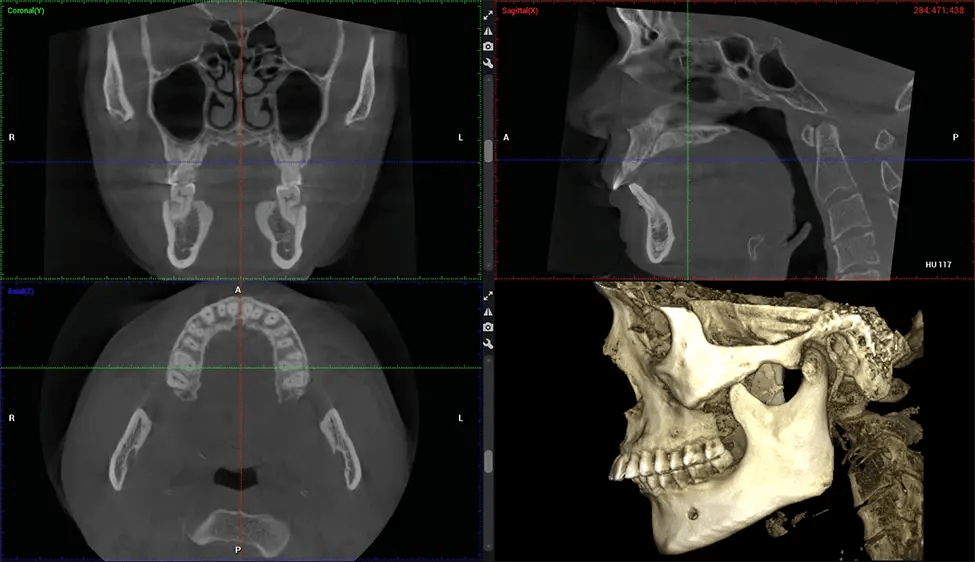

Cone Beam Computed Tomography (CBCT) is an advanced imaging technique used in dentistry and maxillofacial surgery to obtain detailed 3D images of the oral and maxillofacial structures. At Dr G Dental Studio, our CBCT scanners utilize a cone-shaped X-ray beam and a specialized detector to capture images from different angles. A computer then combines these images to create a 3D representation of the patient’s oral anatomy.

This 3D scan, called cone beam computed tomography, gives your dentist a more complete image of your oral anatomy and disease processes than a traditional X-ray. Unlike conventional X-rays, which capture a 2D image of your mouth from various angles, a 3D scan takes multiple digital X-rays for one image. It provides a complete view of your jaw, teeth, nerves, and soft tissues. This enhanced view allows dentists to detect minor issues not visible in traditional 2D scans, such as impacted wisdom teeth or bone fractures in the sinus cavity.

There are many benefits to using CBCT technology, especially compared to the traditional 2D X-ray format. One of the most significant advantages of CBCT scans is that they provide much more information than traditional X-rays. A scan lets your dentist see images from all angles of your jaw and mouth, including your sinuses, nasal cavity, cheekbones, and other surrounding areas. This added information helps your dentist craft a comprehensive treatment plan that addresses all aspects of your oral health.

Another significant benefit is that 3D imaging provides more precise images of your bone structure. These images are more detailed, providing you with a more accurate diagnosis. An accurate diagnosis means better treatment for you.

After the scanning process, the captured X-ray images are processed by the CBCT software, which applies algorithms to reconstruct a detailed 3D image of the scanned area. The software compiles these individual X-ray images and creates a digital 3D representation of the patient’s anatomy. The reconstructed 3D CBCT image can be viewed and analyzed by the dentist or radiologist. This image can be manipulated, rotated, and zoomed in or out to examine specific structures and evaluate the patient’s condition.